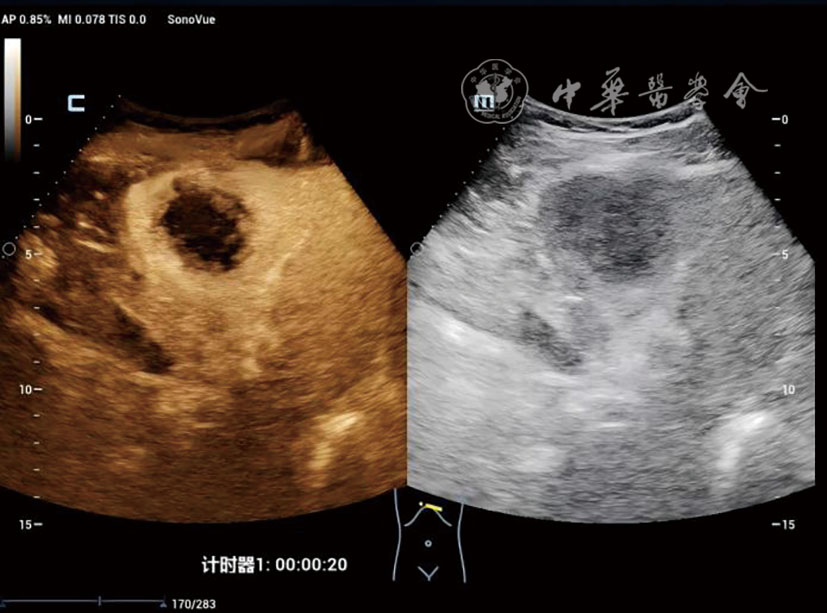

The DPHCC group showed significantly higher rates of serum alpha-fetoprotein (AFP) ≥400 ng/ml (48.4% vs 15.0%, P=0.002) and microvascular invasion (77.4% vs 17.5%, P<0.001) compared to THCC. On CEUS, DPHCC predominantly exhibited heterogeneous enhancement (38.7% vs 15.0%) and rim-like enhancement (16.1% vs 2.5%) in the arterial phase (P=0.003), with earlier contrast agent washout initiation (91.94±37.58 s vs 131.65±59.71 s, P=0.002). Multivariate analysis identified tumor size (odds ratio [OR]=1.019, P=0.002), AFP≥400 ng/ml (OR=2.798, P=0.032), ill-defined margin (OR=3.204, P=0.020), and washout time <120 s (OR=2.221, P=0.049) as independent risk factors for DPHCC.

Multi-parametric CEUS provides critical evidence for noninvasive diagnosis of DPHCC, effectively differentiating it from THCC and optimizing personalized clinical management.